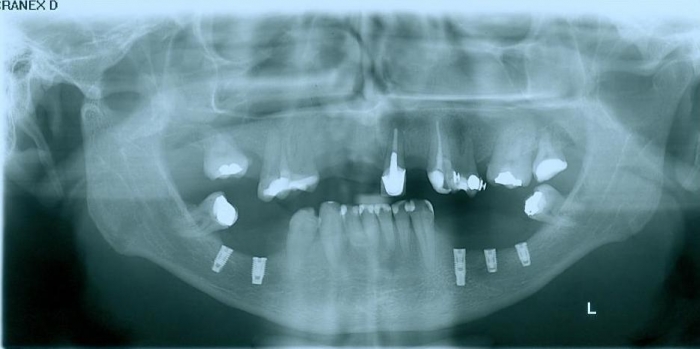

Raio - x implantes inferiores em Junho de 2011  - Clínica Cliniface

Raio - x implantes inferiores em Junho de 2011